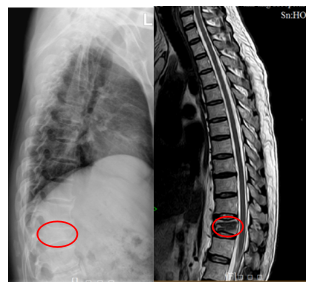

微创 | 高处坠落致胸椎爆裂性骨折,手术

近日,骨科郑明辉副主任医师团队成功实施我院首例经皮穿刺椎弓根...